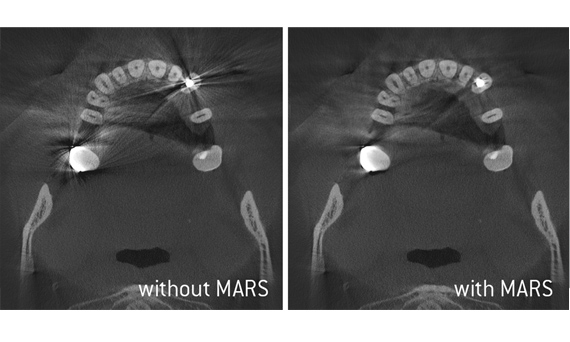

With all of our Dentsply Sirona 3D imaging units, Axeos and Orthophos S 3D, you get state-of-the-art imaging processes designed for optimal clinical diagnostic support. When capturing a 3D X-ray with one of our devices, several hundred individual images are taken and then this data is combined within the matter of seconds to create a final 3D image of the jaw area for your diagnosis. The practitioner is then able to take a “virtual tour” of the scan and assess the data from every dimension.